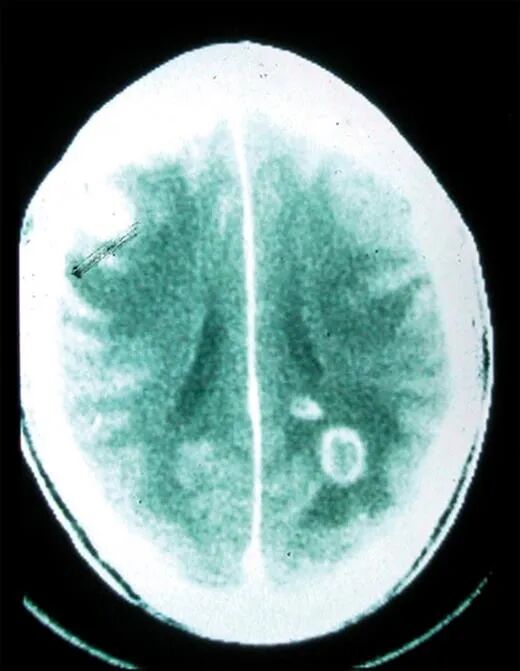

弓形虫感染人类大脑 图片来源:Sullivan & Jeffers, 2012

随后,研究者想直接观察弓形虫到底能对人类精子产生什么样的影响,于是开展了体外实验。他们将弓形虫与健康捐献者的精子放置在一起。结果发现,仅 5 分钟后,22.4% 的精子就失去了头部,仿佛被斩首了一般;而 10 分钟和 15 分钟后,无头精子的数量(相比于对照组)分别增加了 4 倍和 8 倍。

弓形虫“斩首”人类精子 图片来源:Rojas-Baró et al, 2025

在扫描电子显微镜下可以观察到,精子尾部或头部存在弓形虫速殖子,一些精子的尾部呈现出扭曲卷起或直角的姿态。被感染的精子线粒体功能严重受损,一些区域的线粒体甚至完全被清除,这极大地影响了精子的活力。